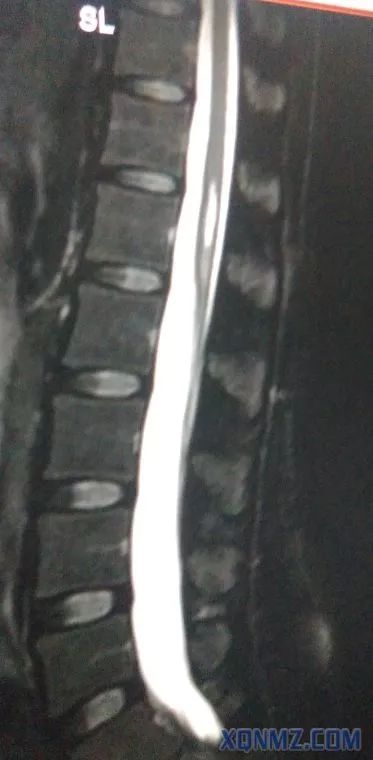

下面是我工作中在影像科学习时发现了一例中年女患,脊髓变异,终止于L3-4,而不是L1下缘,此患者要是做腰麻后果不堪设想,相信大家做腰麻时不可能所有的患者都术前做磁共振检查吧。